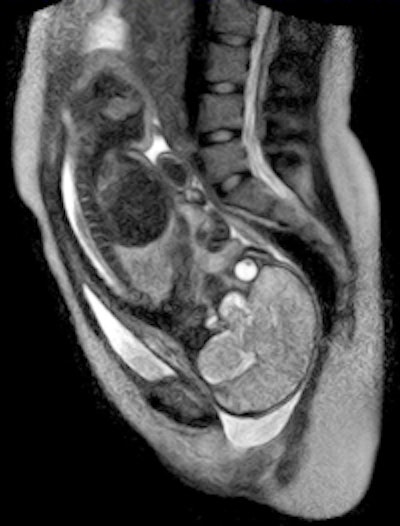

German physicians and healthcare providers at Charité University Hospital in Berlin recently followed the birth of a child on an open MRI system.

| Image courtesy of Charité University Hospital. |

The hospital reported that the birth on November 20 was without complications and both mother and baby are doing well. The baby, a boy, weighed 2,585 grams (5.7 lb) and was 47 cm (18.5 inches) in length.

The study was performed as part of a two-year research and development project on open MRI involving a novel fetal monitoring system that allowed the monitoring of the child's heartbeat during the birth process. The researcher team, led by radiologist Ulf Teichgräber, MD, noted that the open design of the scanner provided easy access to mother and child during the study.

The research team plans to explore the birth process and movements of the unborn child and the mother's pelvis to better understand why approximately 15% of pregnant women need a cesarean section due to the baby not moving properly into the birth canal.